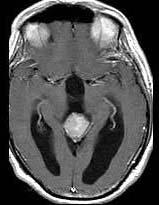

问题 15岁,男,头痛、呕吐,步态不稳,眼球震颤,性发育异常,MRI检查如图,最可能的诊断()

选项 A.松果体钙化 B.松果体瘤 C.脑膜瘤 D.生殖细胞瘤 E.畸胎瘤

答案 B